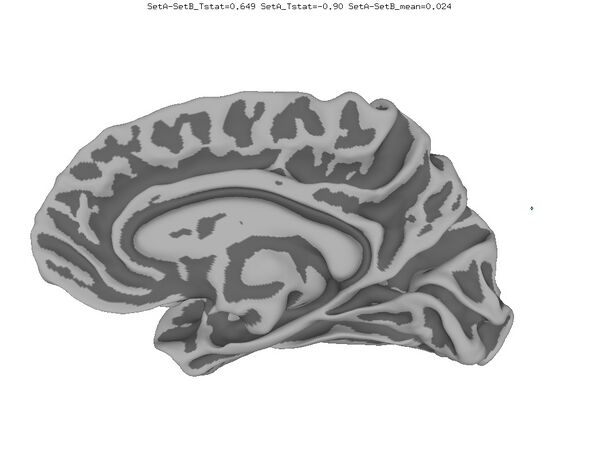

Functional Data

Functional data of the Mouth vs. Eye contrast mapped to the average surface. It is hard to quantify the difference, but one way is to compare the maximum statistical values; with better intersubject alignment, these would presumably increase.

1. NEW: Max t-value for Mouth: 9.3 Eye:10.1 Eye vs Mouth: 5.6

2. OLD: Max t-value for Mouth: 7.9 Eye:8.8 Eye vs Mouth: 5.8

data from Zhu LL, Beauchamp MS. Mouth and Voice: A Relationship between Visual and Auditory Preference in the Human Superior Temporal Sulcus. Journal of Neuroscience 8 March 2017, 37 (10) 2697-2708; DOI: https://doi.org/10.1523/JNEUROSCI.2914-16.2017. Click here to download the PDF. Surface averages were not used in this paper so the bug did not affect the published results.

New

Old